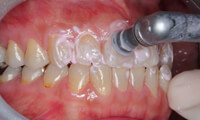

● スケーリング(歯石取り)

「スケーラー」と呼ばれる器具を用いて、歯周病の原因となる歯垢を除去します。軽度の歯周病に対して行う治療です。歯石は歯磨きでは取れないので、定期的に歯科医院で取ってもらいましょう。

● PMTC(プロによる歯のクリーニング)

PMTCとは、Professional(専門家が) Mechanical(専用の機械で) Tooth(歯面を) Cleaning(クリーニングする)の略で、歯科医師・歯科衛生士が機械を使って行う、本格的な歯のお掃除のことです。

お口の中にはホームケアだけでは取り切れない歯石・汚れ・バイオフィルム(口の中の細菌の巣)などが付着しています。毎日の歯磨きにプラスして、定期的に歯科医院へ通い、歯にこびりついた頑固な汚れを落としていくことが大切です。